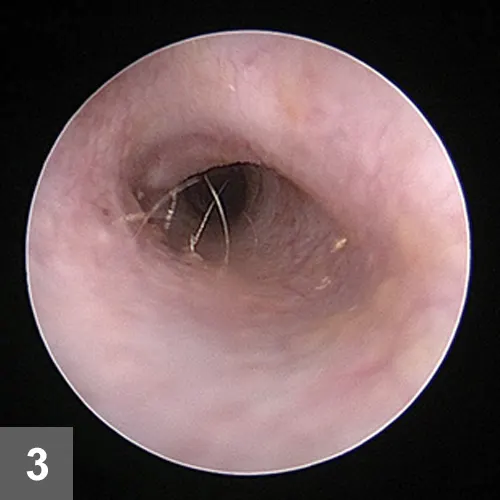

Figure 3. Eight weeks after initial presentation, the otitis externa had resolved and the tympanic membrane could be visualized.

At the second recheck, 8 weeks after initial presentation, Beignet’s pruritus score was 0. Mild hypotrichosis was present on the neck. The ears were nonpainful and pliable on palpation. The ear canals demonstrated scant erythema. Tympanic membranes were visualized and normal (Figure 3).

Repeat cytology of the ears revealed no etiologic agents.